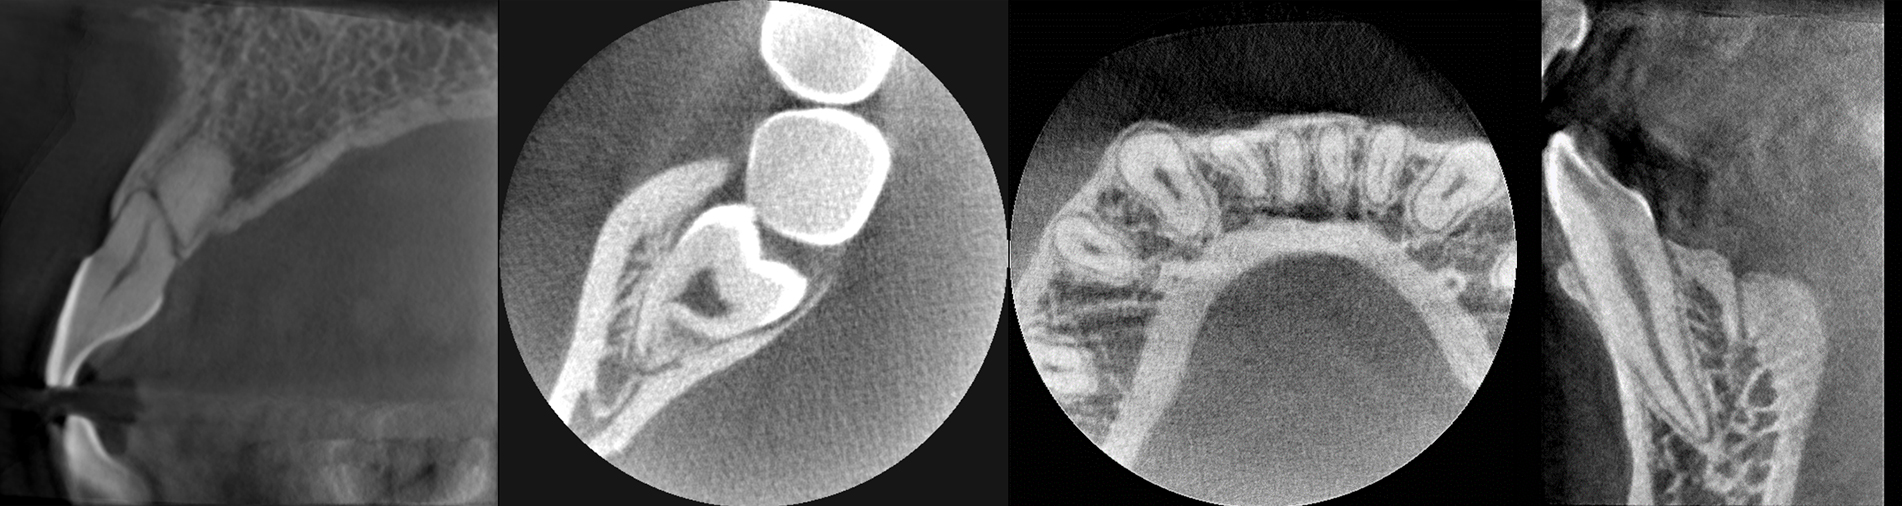

歯科用CTを用いた正確な診断

歯科用CTは、顎の骨の状態を3D画像で詳細に把握できる先進的な機器です。これにより、骨の厚さや密度を正確に確認でき、インプラント治療の計画をより精密に立てることができるため、治療の成功率を大幅に向上させます。

複雑な歯の根の状態も精密に診断できるため安全なインプラント治療に必須です。

シミュレーションソフトで事前確認

取得したCT画像をもとにシミュレーションソフトで治療計画を作成し、インプラントの埋入位置や角度を事前に確認します。このシミュレーションにより、手術の正確性が増し、歯茎を切開する範囲を最小限に抑えることが可能です。その結果、術後の治りが早まり、身体への負担も軽減されます。

サージカルガイドを使用

インプラント埋入時には、精密なマウスピース型のサージカルガイドを使用します。このガイドにより、インプラントの位置や角度が正確に決まり、神経や周囲の組織を傷つけることなく、安全に治療を進めることができます。また、歯茎への負担も最小限に抑え、患者さんにとってより安心・快適な治療を提供しています。